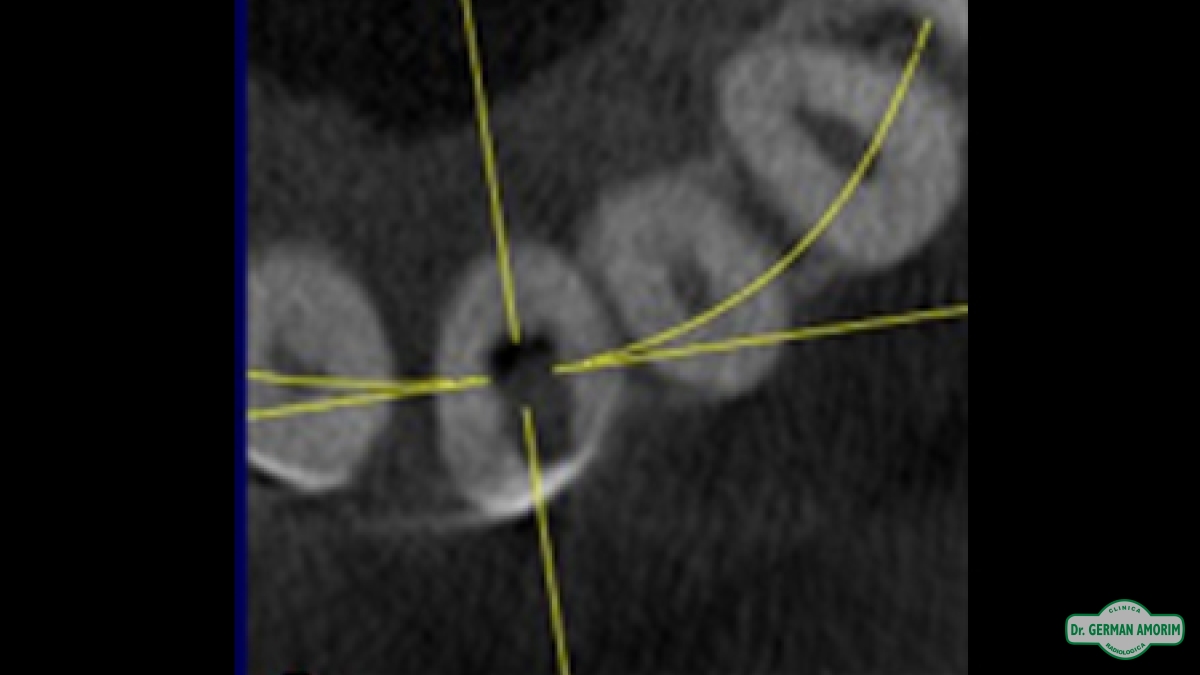

La radiografía tridimensional también tiene mucha utilidad de en Endodoncia como se ve en este caso que detallamos a continuación.

El profesional no podía encontrar el conducto en la radiografía periapical estándar. Al ser bidimensional no lo veía y por eso le indicó una tomografía volumétrica digital (TVD).

En la imagen tridimensional se pudo apreciar dónde estaba el conducto . Como se ve en las imágenes tridimensionales faltó muy poco para hacer una perforación ya que el profesional se estaba yendo hacia vestibular. Gracias a la TVD se pudo identificar y hacer el tratamiento de endodoncia sin problemas.